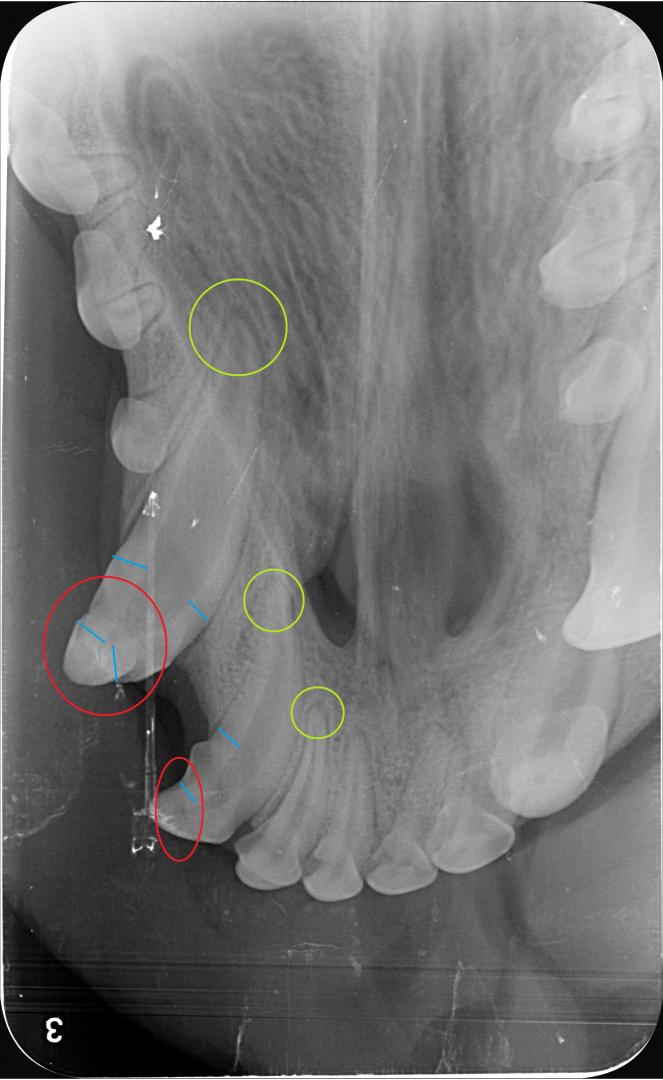

radio croc

Dans le cas d'Alphonse :

- l'apex est fermé (cercle vert) sur les 3 dents concernées ; aucun abcès n'est visible et donc la pulpe ne présente pas de signe de contamination (vérifié également par sondage, le canal n'est pas perméable)

- La couche de dentine semble déjà conséquente et suffisante pour donner une chance à la dent (trait bleu) ;

La décision est donc prise de tenter de la conserver, et de protéger la pulpe en déposant une couche de résine pour combler les surfaces abîmées du croc.